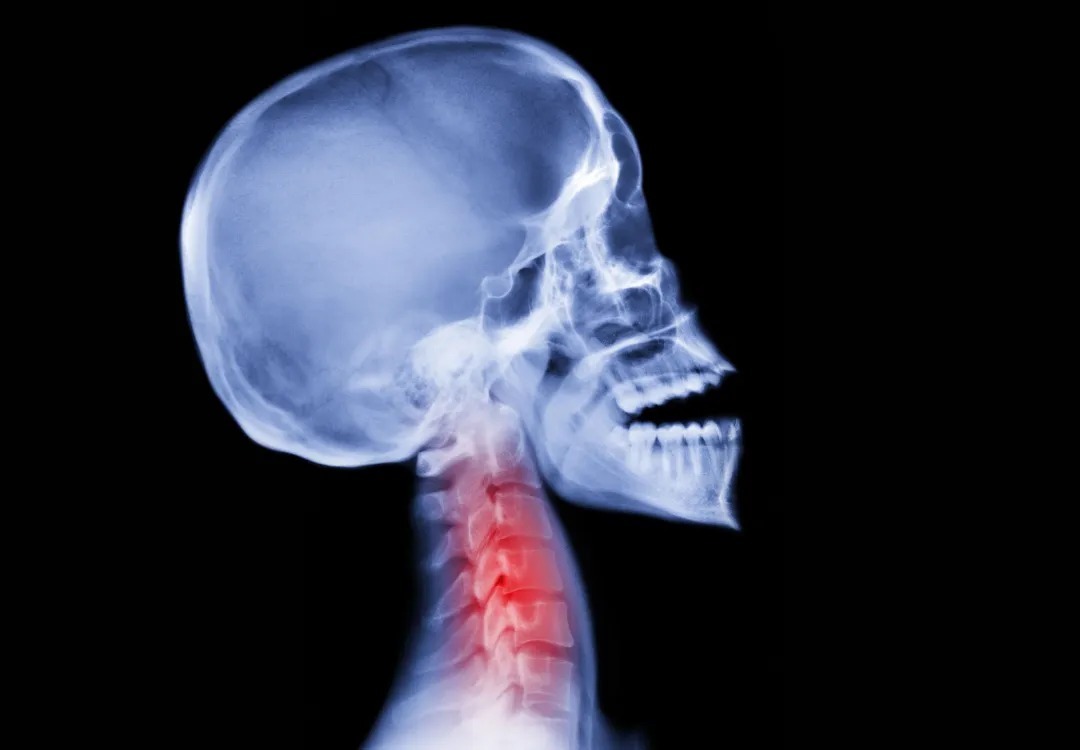

در بدن افراد سالم، این ژن مانع از رشد بیش‌ازحد استخوان‌ها می‌شود؛ اما در مبتلایان به اف‌او‌پی، رشد کنترل‌نشده‌ی بافت استخوانی در اطراف مفاصل اتفاق می‌افتد. نشانه‌های اولیه‌ی بیماری اغلب در دوران کودکی ظاهر می‌شوند؛ از جمله انگشتان پای بدشکل و سفتی تدریجی در نواحی گردن و شانه‌ها که در نهایت به سایر قسمت‌های بدن نیز گسترش می‌یابد.

تشکیل بافت استخوانی در اطراف عضلات قفسه سینه می‌تواند تنفس را دشوار و دردناک کند و خطر مرگ را افزایش دهد. بررسی‌ها نشان داده‌اند که میانگین سنی مرگ در مبتلایان، حدود ۴۰ سال است و بیش از نیمی از این افراد به دلیل نارسایی قلبی و تنفسی فوت می‌کنند.